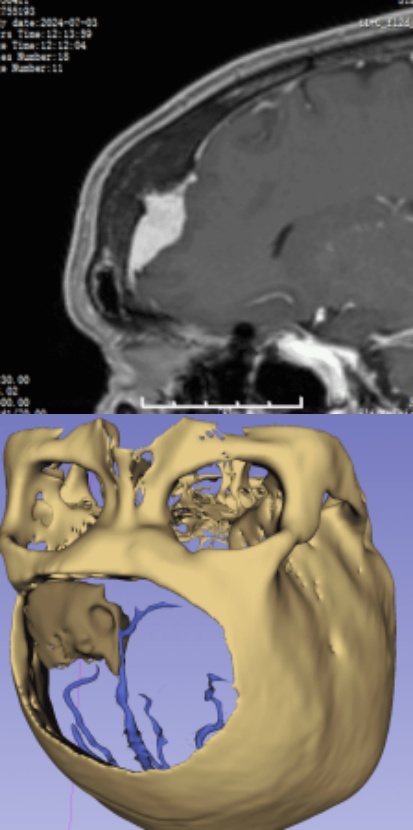

MRI

CT

影像重建

腫瘤與靜脈、矢狀竇的關系

靜脈影像重建

CT重建

左額內外板可見骨質增生

■ 初步診斷:左額部凸面-矢狀竇旁腦膜瘤